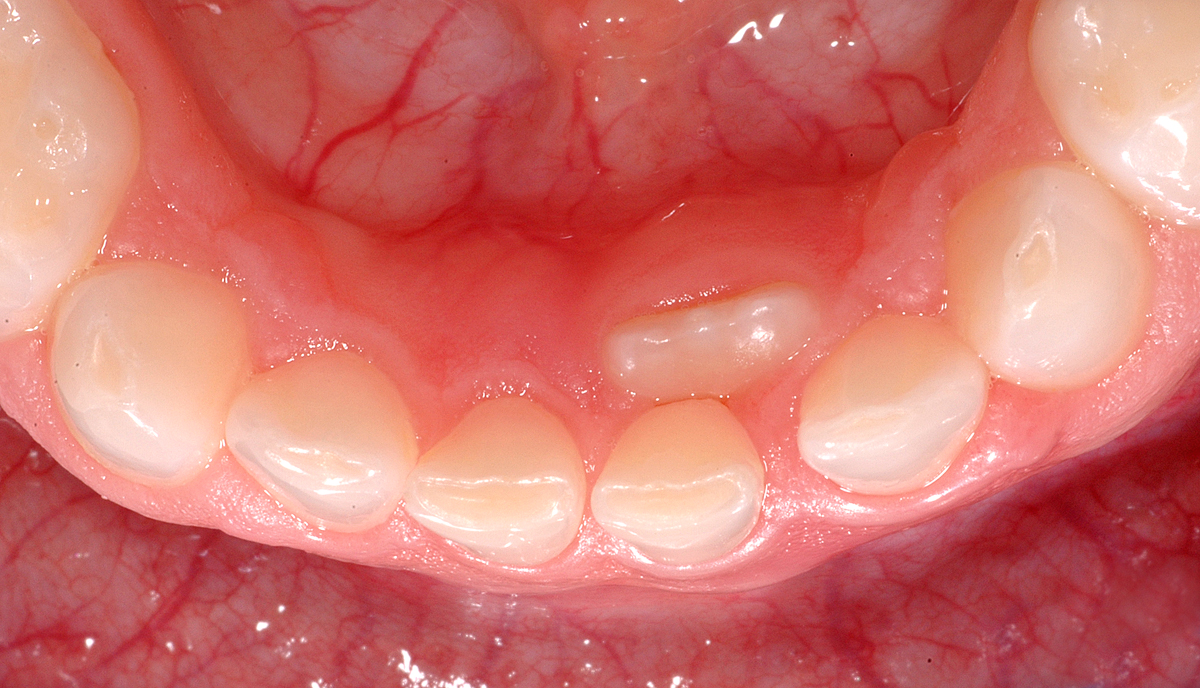

Anbei noch ein Fall, bei dem der Milchzahn noch da und der bleibende Zahn schon im Durchbruch ist.

Der Fall ist ähnlich wie die oben gezeigten.

Auch bei Fällen wie diesem muss man nicht gleich sofort einen Termin beim Zahnarzt oder der Zahnärztin vereinbaren. Geben Sie dem Zahn noch etwas Zeit (ein bis drei Monate), ihr Kind soll jeden Tag fest dran rumwackeln. Wenn der Zahn dann immer noch fest ist, so kann man ihn auch zu einem späteren Zeitpunkt noch entfernen.

Es wird oft gefragt, ob denn der Zahn dann nicht dort innen stehen bleibe, wenn man den Milchzahn nicht entfernt. Auch das ist kein Problem, denn in den meisten Fällen wird der Zahn später durch den Druck der Zunge genügend weit nach vorne in die Lücke gestossen.